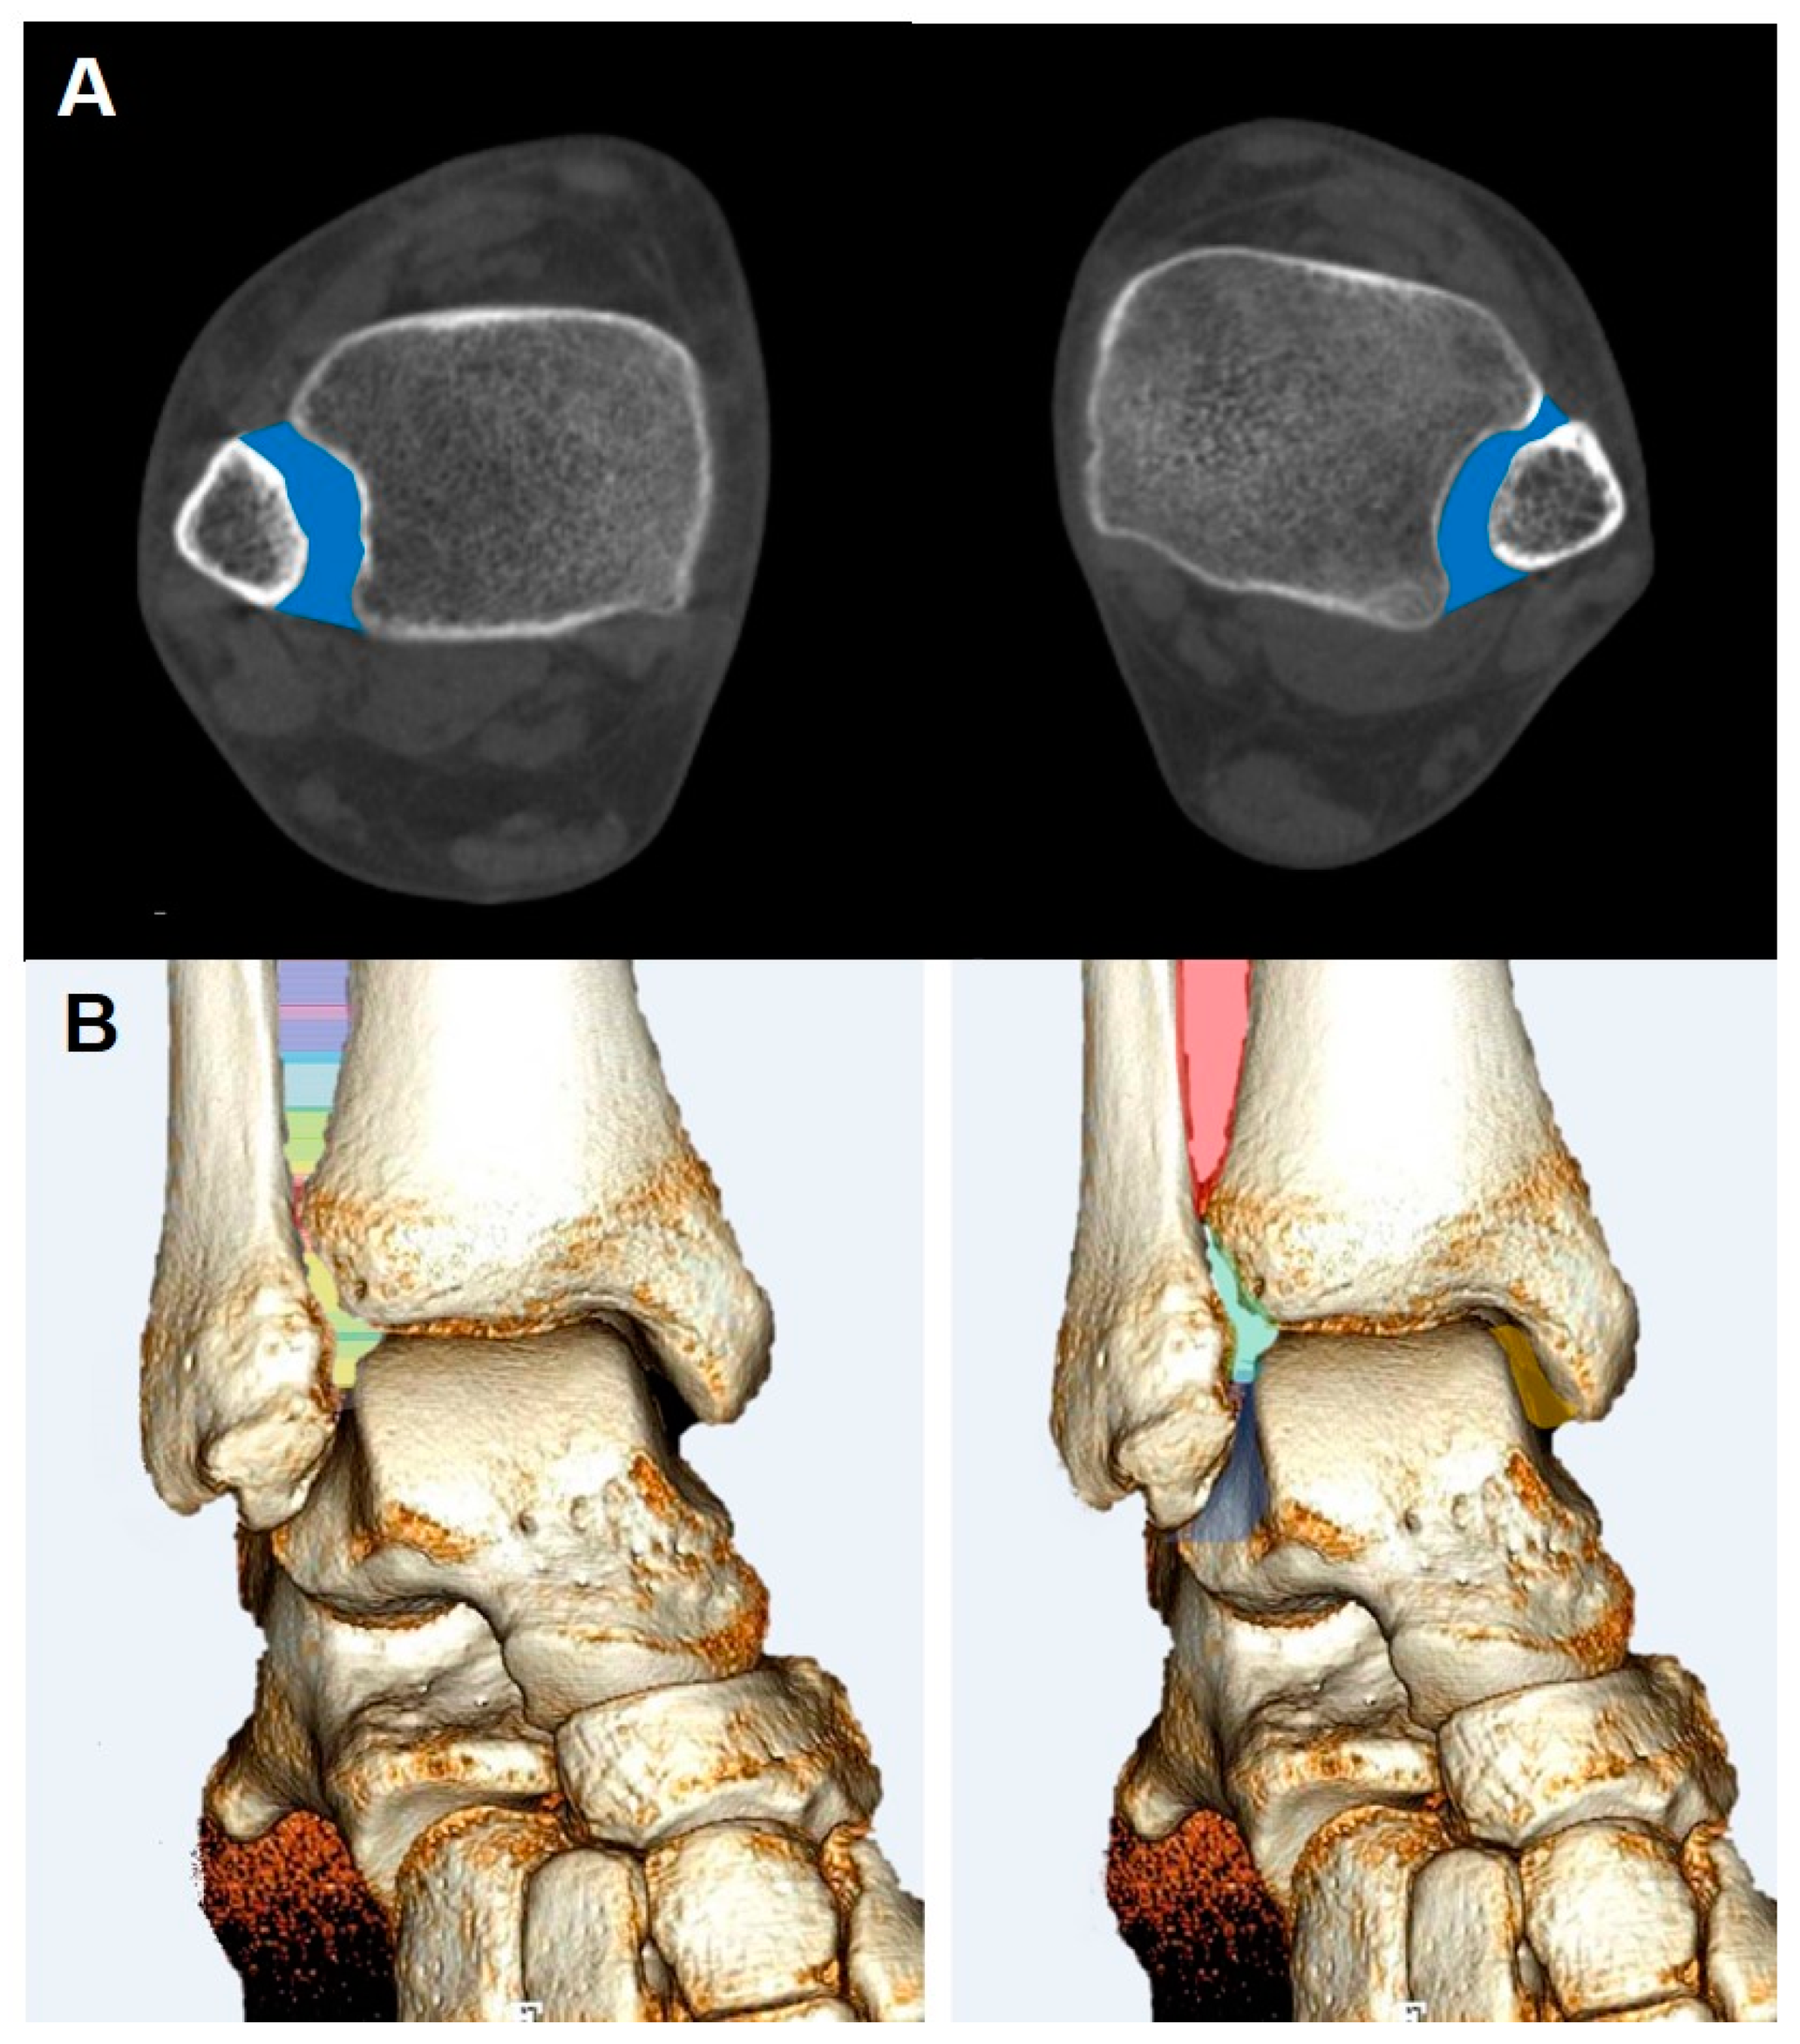

3.2. Syndesmosis Injury